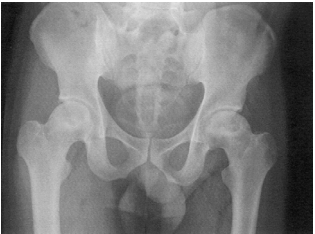

45 47 歲葉先生抱怨左髖部疼痛已經兩年,症狀反覆發作,劇烈活動後以及夜間均會加重症狀。醫師體 檢時發現 4 字試驗呈陽性,進一步 X 光檢查如圖所示,則此患者之疾病與下列何者最不相關?

(A)酗酒 (B)長期服用類固醇 (C)潛水 (D)梅毒